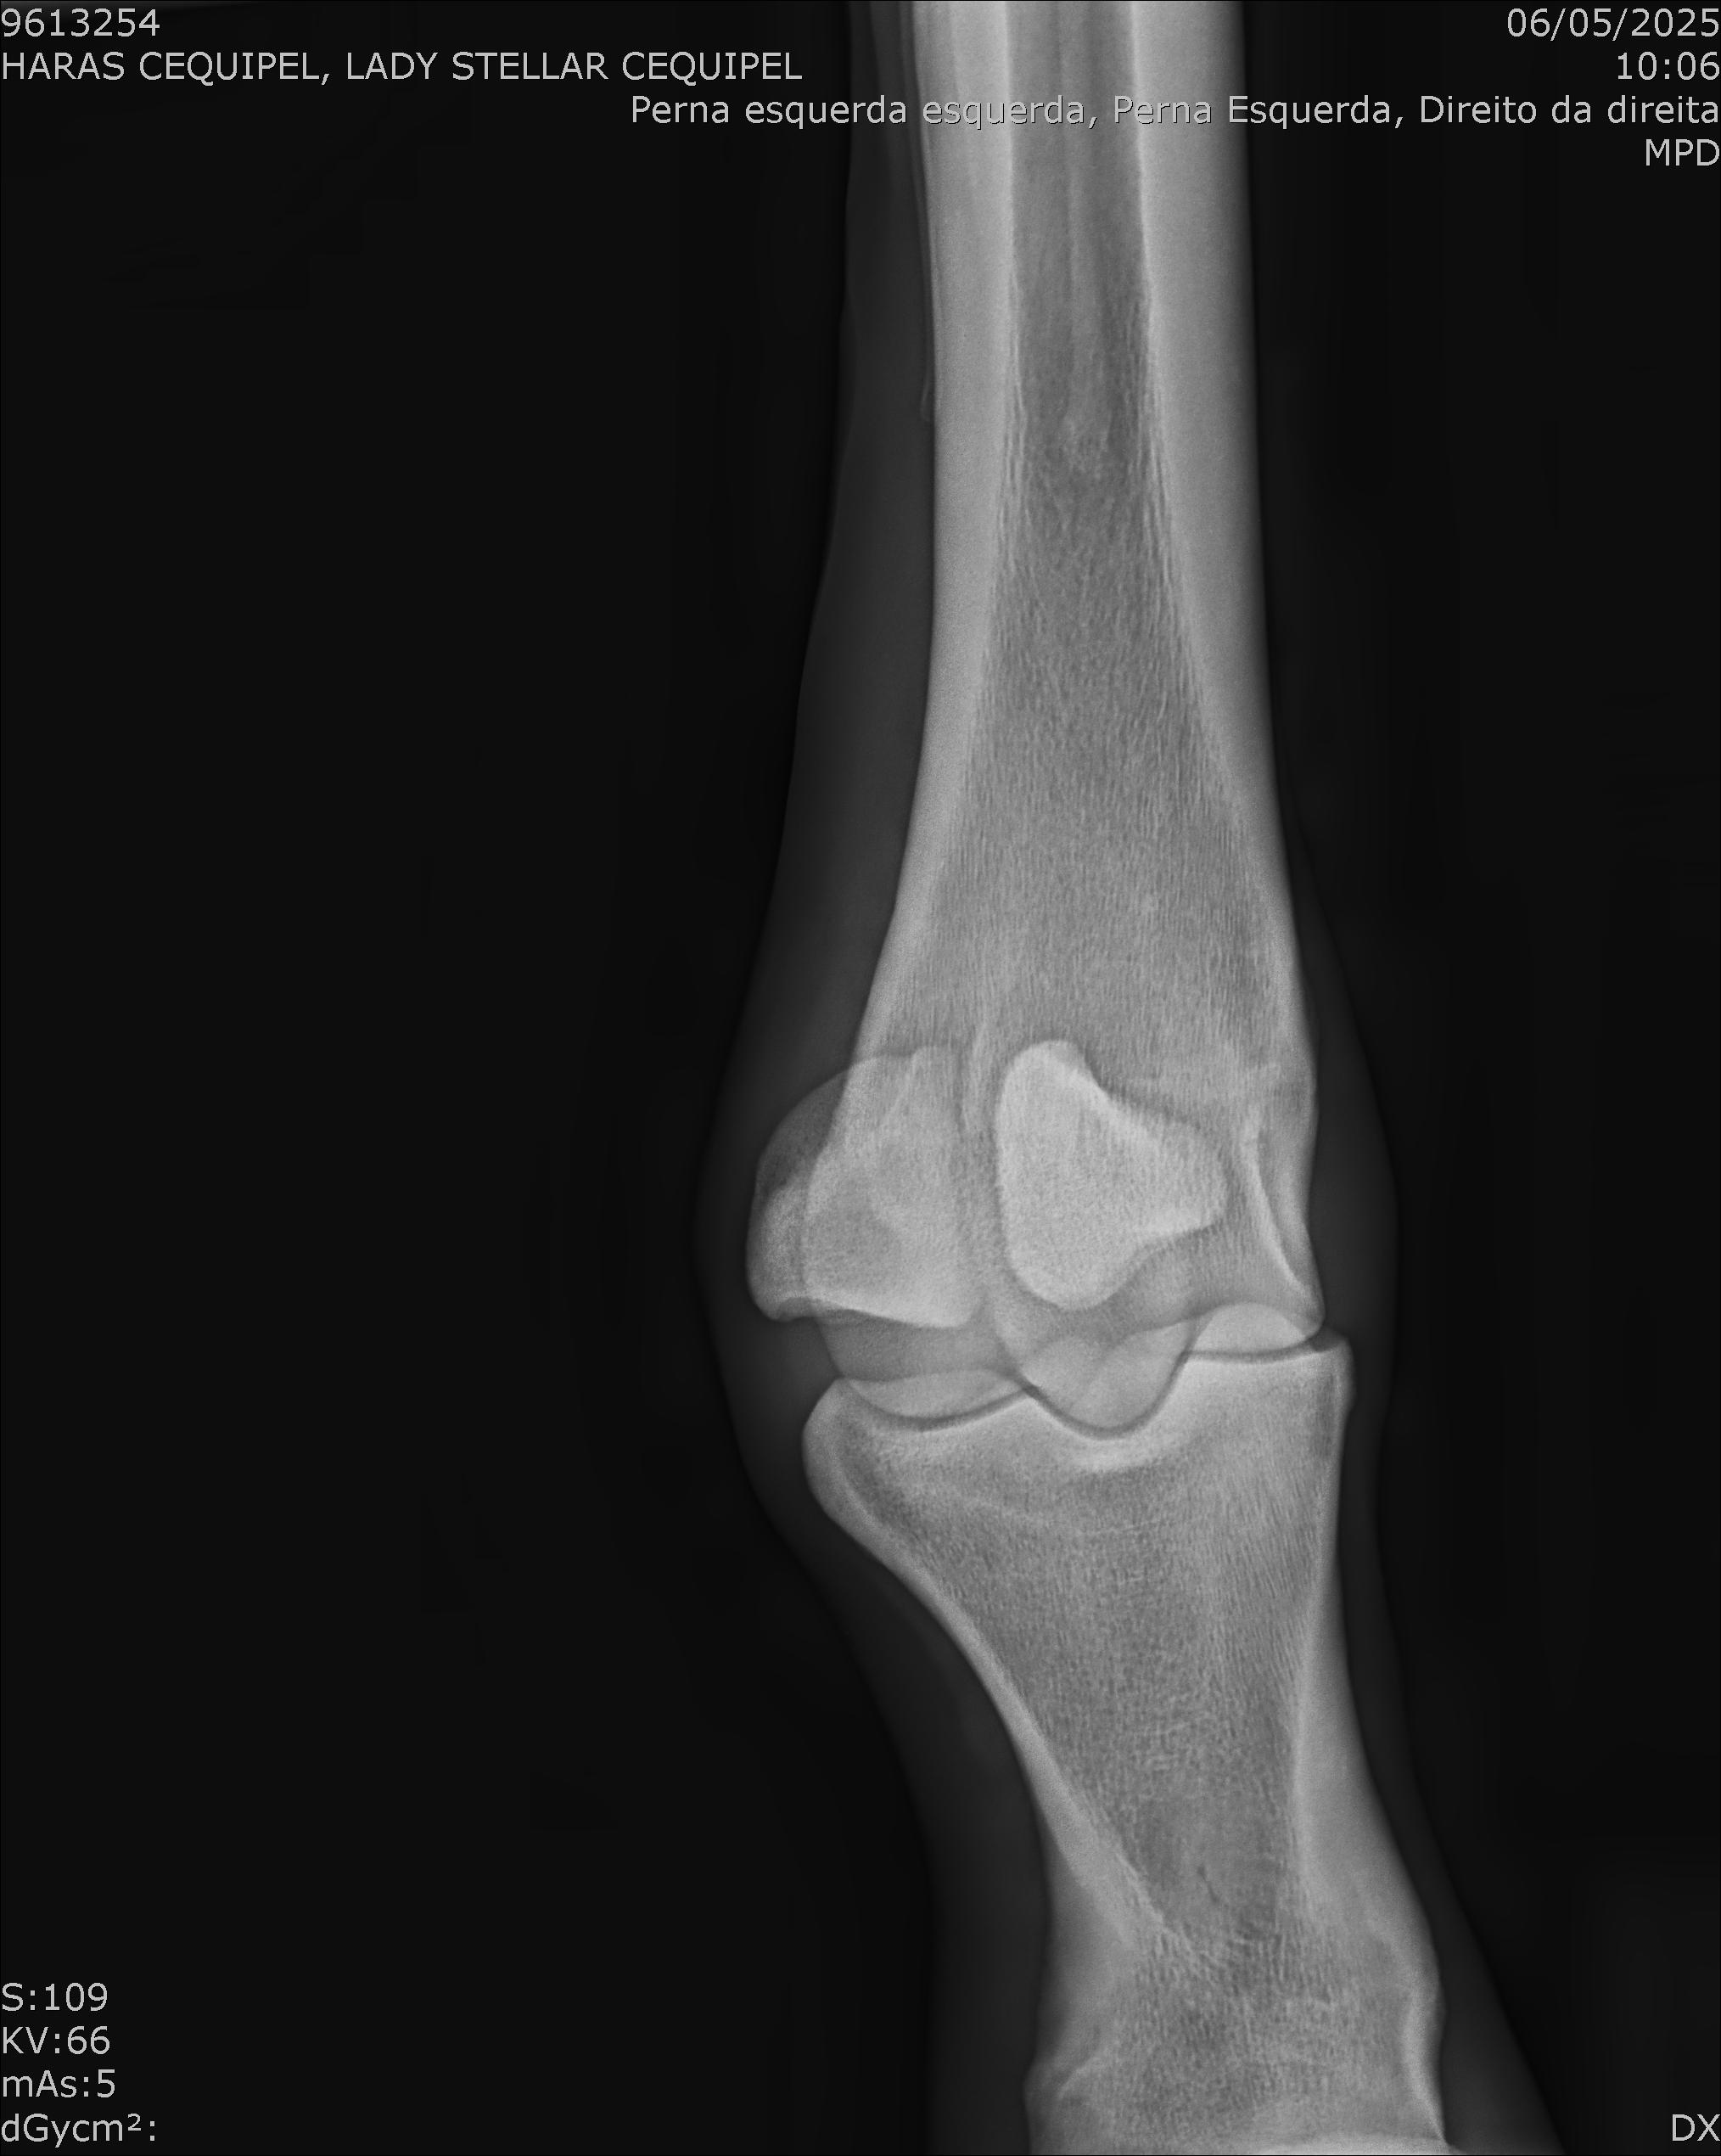

:: RAIOS-X DO LOTE